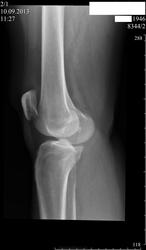

Краевой перелом внутреннего мщелка большеберцовой кости, признаки гемартроза

С перломом согласен, а вот с гемартрозом не очень. Для него надо сделать УЗИ.

Не нравиться, то что вижу излированный костный фрагмент округлой формы-перелом? Если не перелом, то что это?

Я думаю сесамовидная косточка

Пожалуй вы правы, по крайней мере совпадает локлизация тени сесемовидной кости в боковой проекции и этой дополнительной тени в прямой проекции.

Оскольчатый внутрисуставной перелом латерального мыщелка. Насчет краевого не согласна, на боковой видно, что сломано прилично.

Так медиального или латерального, мыщелка или надмыщелка? По мне так нормальная коленка, все на месте

Травмы не было. По клинике типичные проявления артроза.

Одной из причин артроза является травма. Здесь имеются всякие изменения, характерные для посттравматического артроза, переломы костей не обязательны.